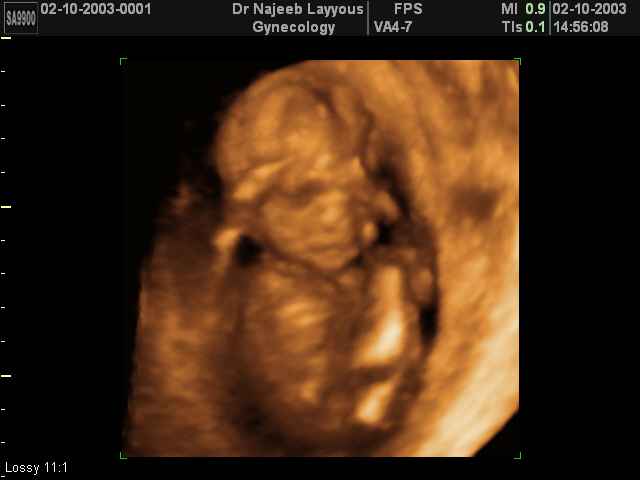

3D second trimestre échographie Photos de numérisation - deuxième partie de la grossesse | Dr N Layyous

3D second trimestre échographie Photos de numérisation - deuxième partie de la grossesse